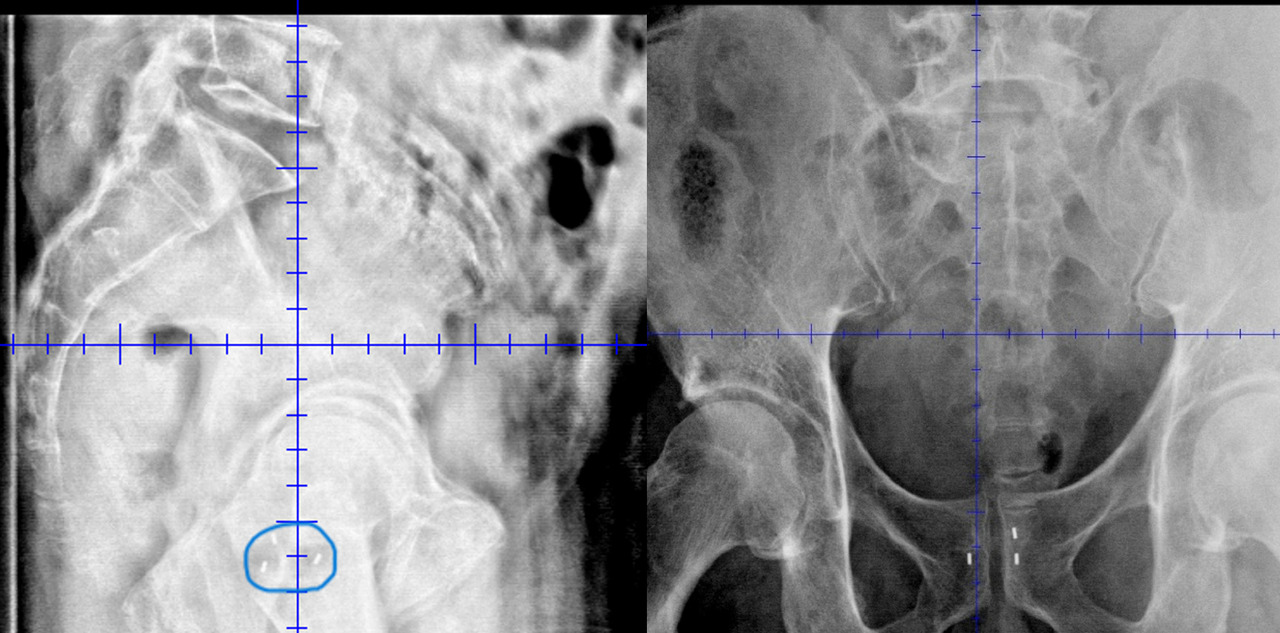

Les imageries traditionnelles de repositionnement fondé sur les structures osseuses ont, elles aussi, été remplacées par des cone beam CT (CBCT) ou scanner embarqué, permettant à chaque séance de se repositionner au mieux sur la cible prostatique et d’appréhender les modifications anatomiques (remplissage de vessie et de rectum, perte ou prise de poids). Ce mode de repositionnement est nommé Image-guided radiation therapy (IGRT).

Il est également possible d’effectuer, avant la radiothérapie, une mise en place de fiduciaires, ou grains d’or, se figeant de manière définitive dans la prostate, et d’appréhender les mouvements de cette dernière pendant les traitements par un suivi de ces grains d’or, soit avant chaque séance, soit pendant la séance en direct (figure).